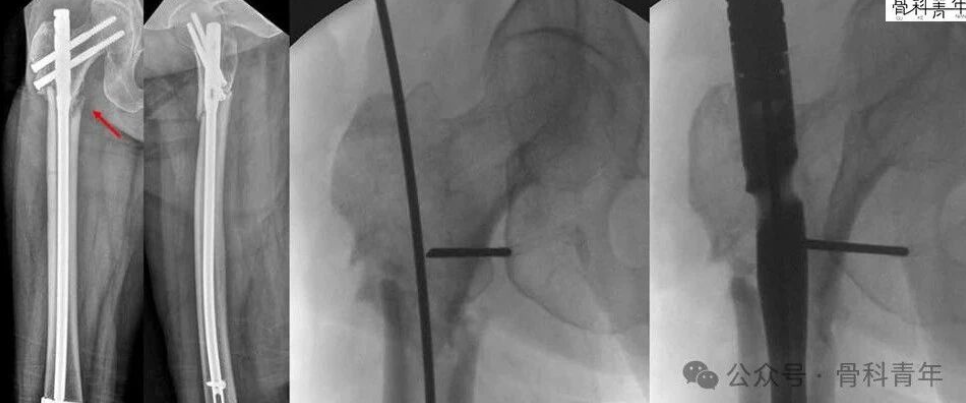

腓骨髓内钉固定减少一个切口可行吗?

1分钟

5.8万人学习